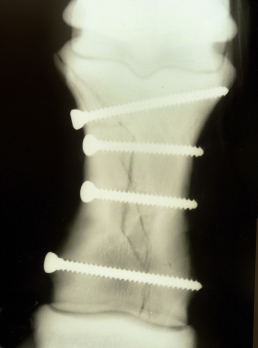

Verklebungen, durch Narben unter der Haut, führen auch zu unphysiologischem Gangbild und verursachen Störfelder, diese beeinflussen negativ den gesamten Körper und somit auch die inneren Organe.